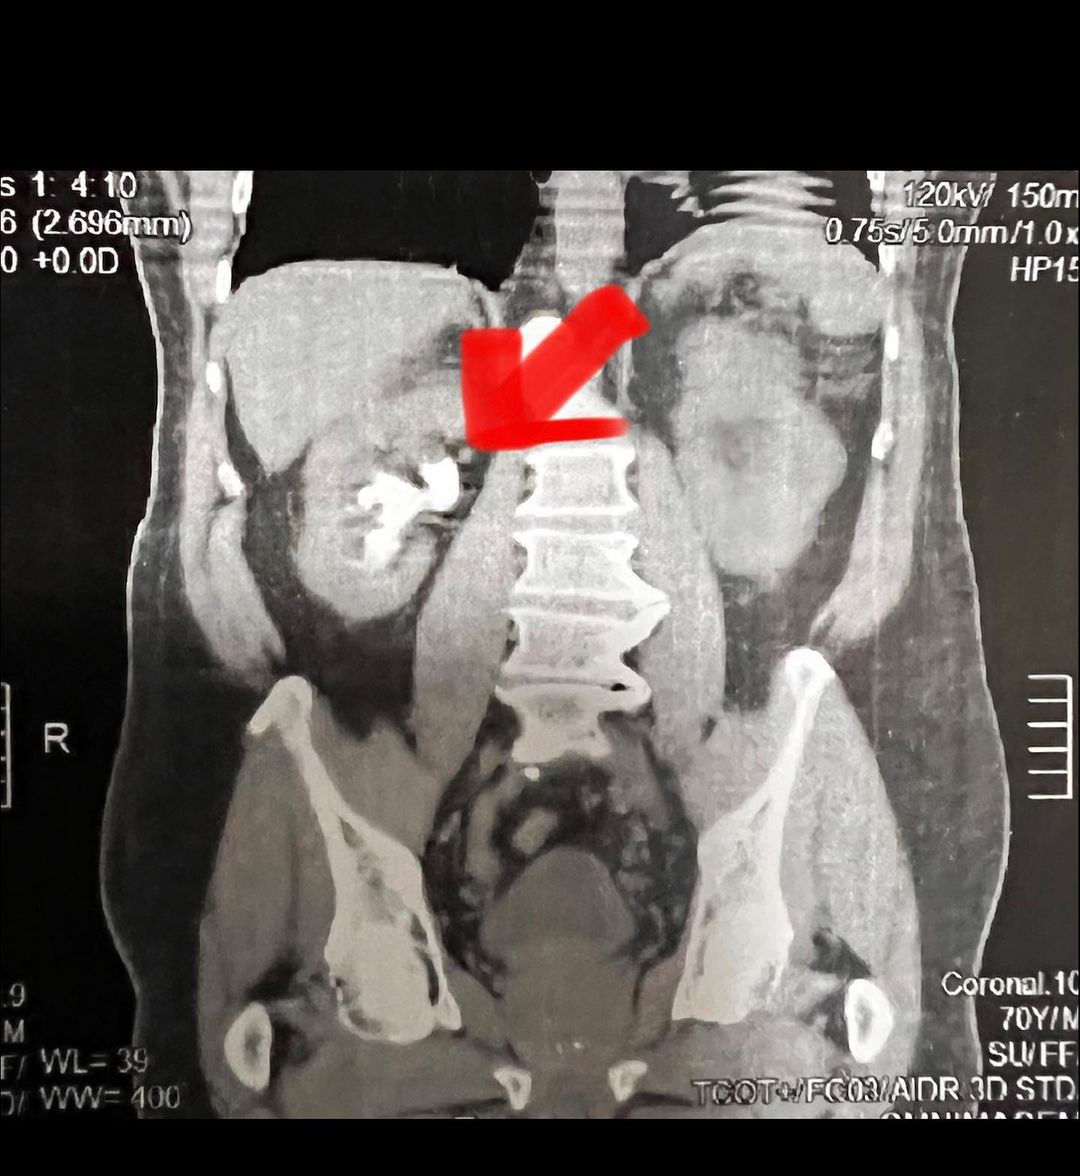

Especialista em Cirurgias Urológicas Minimamente Invasivas, com destaque para Cálculos Renais e Tumores Urológicos.

Imagens